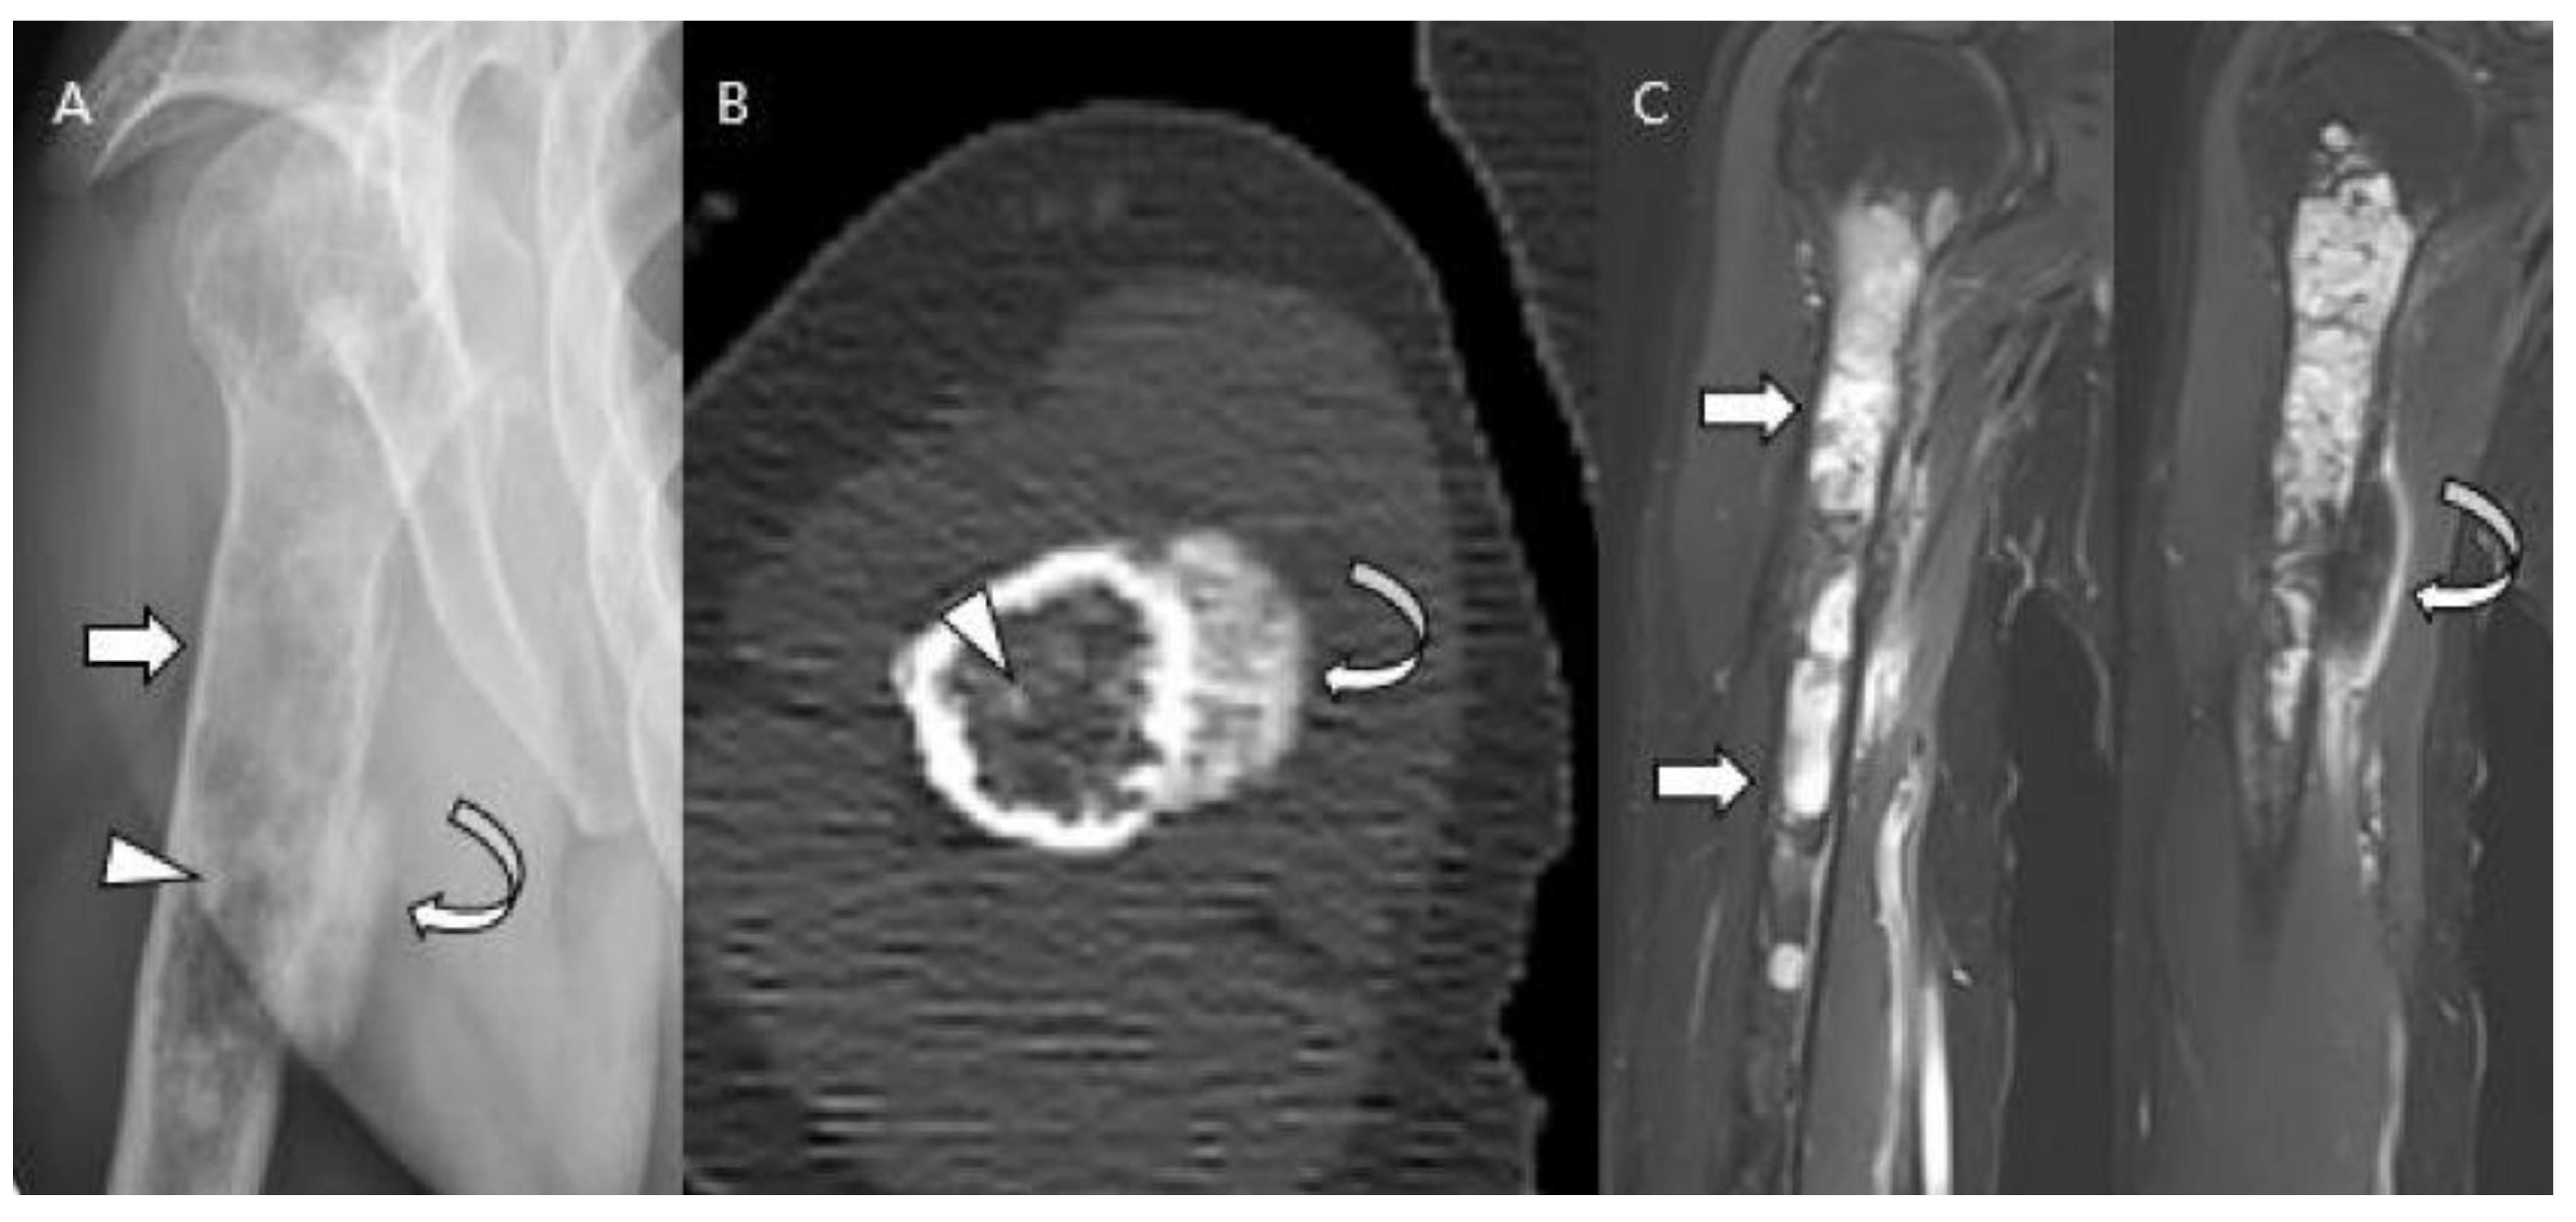

Dedifferentiated chondrosarcoma is characterized by a conventional low-grade chondrosarcoma with an abrupt transition to foci that have dedifferentiated into a higher-grade, more aggressive component [1]. The non-cartilaginous portion is most frequently conventional osteosarcoma (70%) and less commonly malignant fibrous histiocytoma or fibrosarcoma [1,5]. Dedifferentiation can occur in 10–20% of conventional chondrosarcomas [1]. Patients with dedifferentiated chondrosarcomas are older than those with conventional lesions, usually 50–70 years of age (mean age: approximately 60 years) [54,55,56]. Dedifferentiated chondrosarcomas have a poor prognosis. A multicenter review of 337 patients reported that 21% had metastases at the time of diagnosis and the survival of these patients was 10% at 2 years [18,57]. The sites of involvement parallel those of conventional intramedullary chondrosarcoma, with common locations including the femur (35% of cases), pelvis (29%), humerus (16%), scapula (6%), rib (6%), and tibia (5%) [54,55,56]. The radiographic features of dedifferentiated chondrosarcomas are tumor bimorphism including aggressive bone destruction with extraosseous soft tissue extension, associated with an underlying cartilaginous lesion [17]. The imaging findings vary depending on the areas of high-grade transformation [1,58]. Tumors can be classified into three types based on radiographic findings: type 1, radiographic features the same as those of a central chondrosarcoma, with the addition of a suspected region with dedifferentiation; type 2, the tumor resembles the underlying benign enchondroma, but with destructive changes and/or a large soft tissue mass; and type 3, high-grade destructive lesions of the bone without signs of a cartilaginous component [56]. CT and MRI may reveal two distinct areas with differing intrinsic characteristics [1] (Figure 13). This bimorphic pattern is valuable in targeting the high-grade region during image-guided needle biopsy [59].

Figure 13.

Dedifferentiated chondrosarcoma of the humerus in a 54-year-old man. (A) Plain radiograph shows an extensive mixed lytic and sclerotic lesion in the humerus with endosteal scalloping (arrow). Note the chondral-type mineralization in the intramedullary cavity (arrowhead) and the densely osteoid-type mineralization at the juxtacortical area (curved arrow). (B) Axial CT scan also reveals the intramedullary chondral-type (arrowhead) and the juxtacortical dense osteoid-type (curved arrow) mineralization. (C) Coronal T2-weighted images with fat suppression show high signal intramedullary lesion (arrows) with osteoblastic extraosseous extension (curved arrow), suggesting a dedifferentiated component of osteosarcoma.